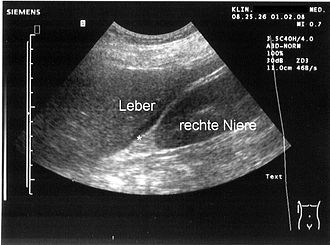

- Ultrazvuk: Manja količina se ovim pregledom može vidjeti ispod jetre ili u Douglasu. G